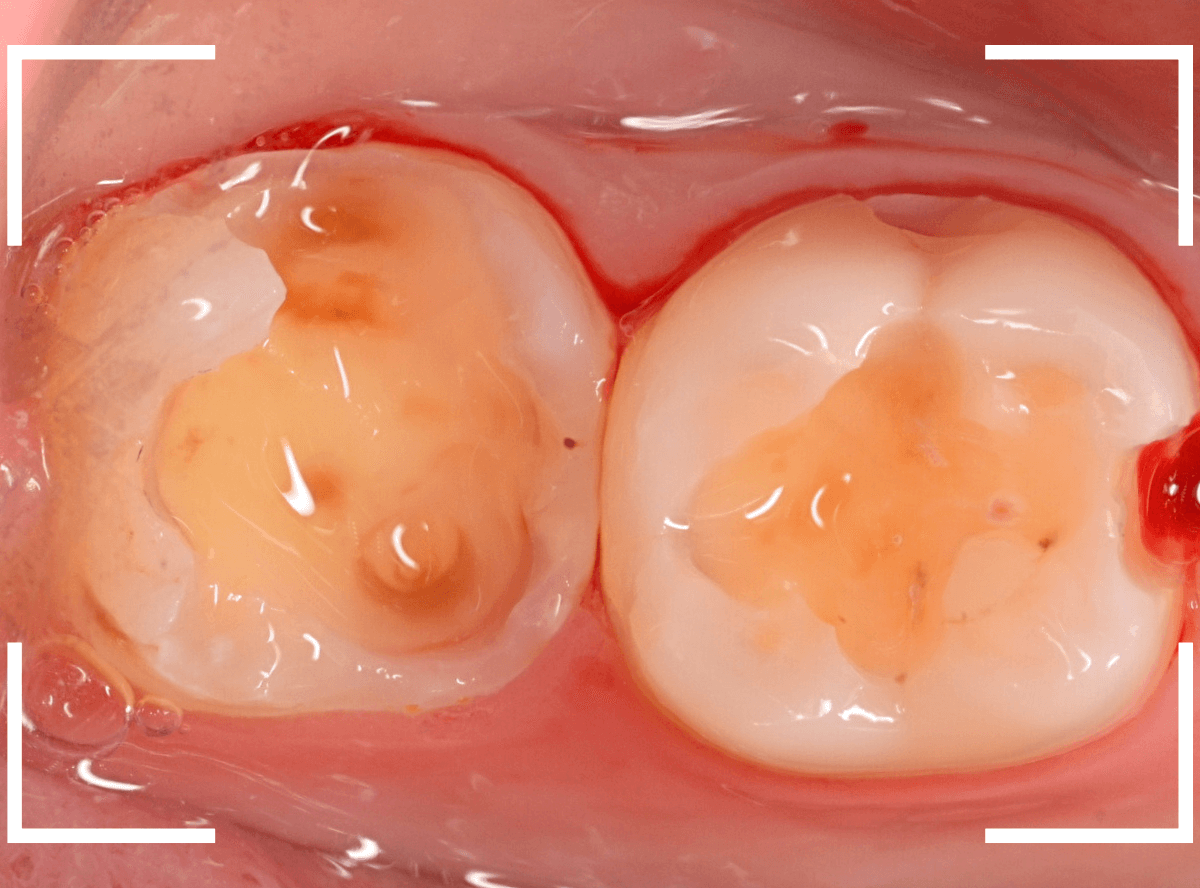

「つめものが欠けたまま長期間放置して、歯がしみる」という訴えで来院された患者さんさんです。

拝見すると、劣化したレジンが欠けて、中で虫歯になっているのがわかります。

・欠けたまま長期間放置した

・しみるという自覚症状がある

事から、中で深い虫歯になっている事が想像されます。

レントゲン写真で確認します。

レジンを外しながら、虫歯を確認します。

慎重にレジンを除去しましたが、途中で露髄(神経が露出する事)しました。

歯の神経の中には、血管も含まれているので、神経が露出すると、このように出血します。

「しみる、痛い」などの明確な強い症状がある場合、このような状況の事が多いです。

今回は出血量が多く、神経を除去する治療(抜髄)の可能性が高いとも感じましたが、できる限り神経を保存する方法を取ることにしました。

神経を保護するお薬をつめて蓋をしてしばらく経過観察します。

神経を除去すると、治療期間が長引くうえに、歯の寿命がとても短くなってしまいます。

できるだけ歯の神経を残すためには、症状が出てからの歯科受診ではなく、定期的なメンテンナンス受診を続けるようにしてください。